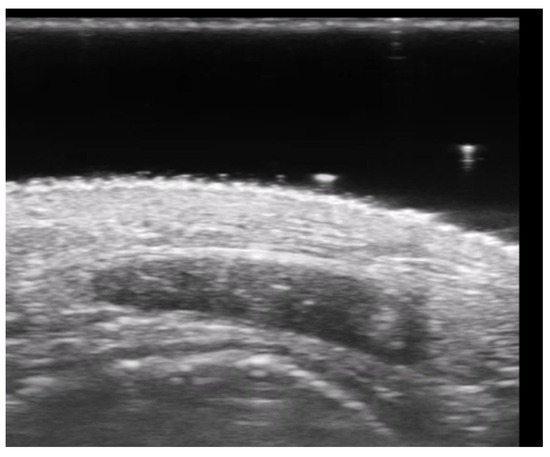

- Gonzalez, C.; Wortsman, X. How to Start on Dermatologic Ultrasound: Basic Anatomical Concepts, Guidelines, Technical Considerations, and Best Tips. Semin. Ultrasound CT MRI 2024, 45, 180–191. [Google Scholar] [CrossRef] [PubMed]